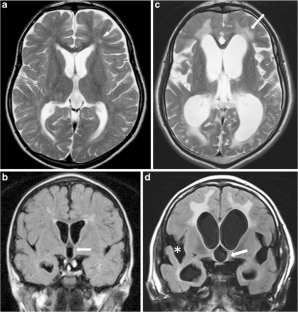

Fig. 3